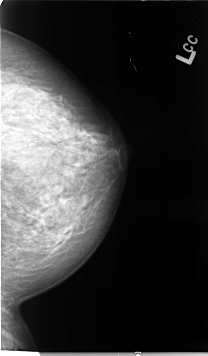

B_3079_1.LEFT_CC

LEFT_CC LINES 4624 PIXELS_PER_LINE 2704 BITS_PER_PIXEL 12 RESOLUTION 50 NON_OVERLAY